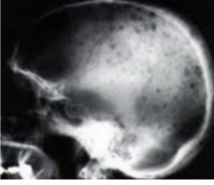

다발골수종 병변. /사진=서울아산병원 |